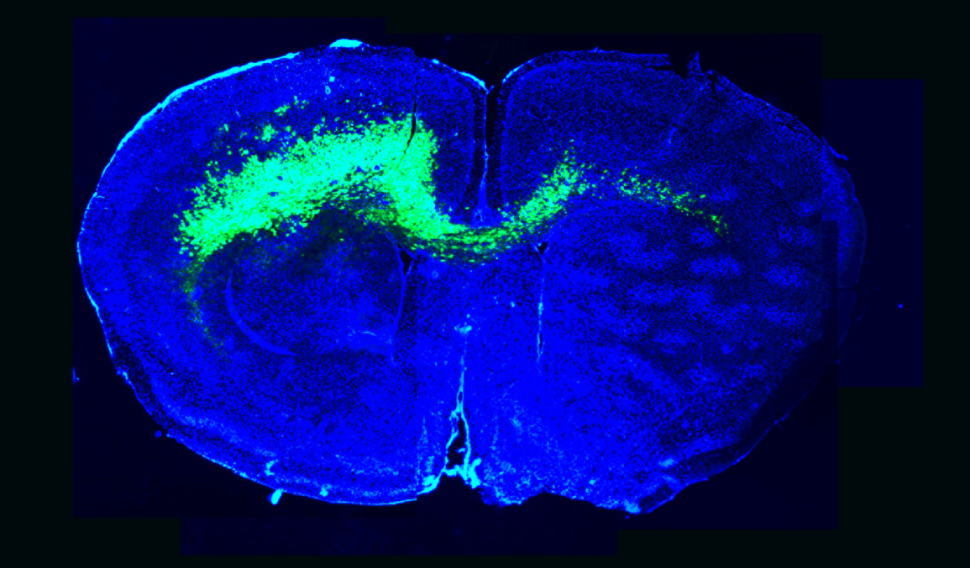

Image of the infiltration of malignant glioma cells (green) throughout a mouse brain (blue) alters brain circuits towards hyperexcitability and sets a stage favorable for glioma growth.

The infiltration of malignant glioma cells (green) throughout a mouse brain (blue) alters brain circuits towards hyperexcitability and sets a stage favorable for glioma growth.

Credit: Emmet Huang-Hobbs and Benjamin Deneen